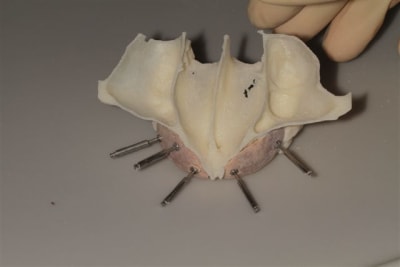

La première diapo est un essai pour justifier le concept (os non destiné à une utilisation greffe)

la deuxième est "tapée" dans une tête de femur de mauvais qualité (rejetée)

la troisième et suivante ce sont "les greffons" définitifs.

L’idée de base est d’obtenir un greffon adapté à la zone à greffer, et de donner plus de chance à la nature de faire son travail de reconstruction.

Une fois les greffons préparés, ils sont traités par un procédé spécifique à Biobank (CO2 supercritique) puis stérilisation (rayons gamma), et vous le verrez la pose devrait être extrêmement simplifiée.